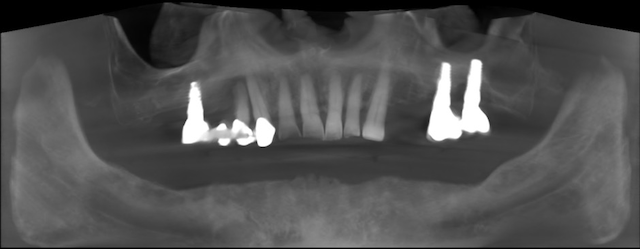

A pácienssel való első találkozás alkalmával 3D CBCT segítségével sikerült tökéletes diagnózist felállítani, amely meghatározta a kezelési tervet is. Az alsó állcsont helyreállításához az All-on-4 technikát alkalmaztuk.

A műtét alatt 4 db Nobel Biocare implantátumot helyeztünk be az alsó állcsontba. A gyógyulási idő lerövidítése érdekében a pácienstől vért vettünk, amiből PRF technológia segítségével vérlemezkékben gazdag frakciót nyertünk ki. Ezt a műtéti területre helyeztük annak zárása előtt. Ez a vérlemezkékben gazdag fibrinháló rengeteg növekedési faktort, fehérvérsejtet és citokint tartalmaz, amely nagymértékben hozzájárul a fájdalommentes és gyors gyógyuláshoz.

A felső állcsont esetében nagymértékű gyulladások voltak a korábbi rossz pozícióban behelyezett implantátumok és fogak körül. A helyzetet tovább nehezítette az előrehaladott fogágybetegség (parodontózis) is, amely következtében a fogak meglazultak, és már nem voltak hosszú távon szájban tarthatóak.

Ezek tudatában a teljes szanálás mellett döntöttünk és hasonló All-on-4 technológiát alkalmaztunk. A felső állcsont esetében 6 implantátumot helyeztünk be. Ebben az esetben is nagy mennyiségű PRF membránt használtunk fel a műtét során.